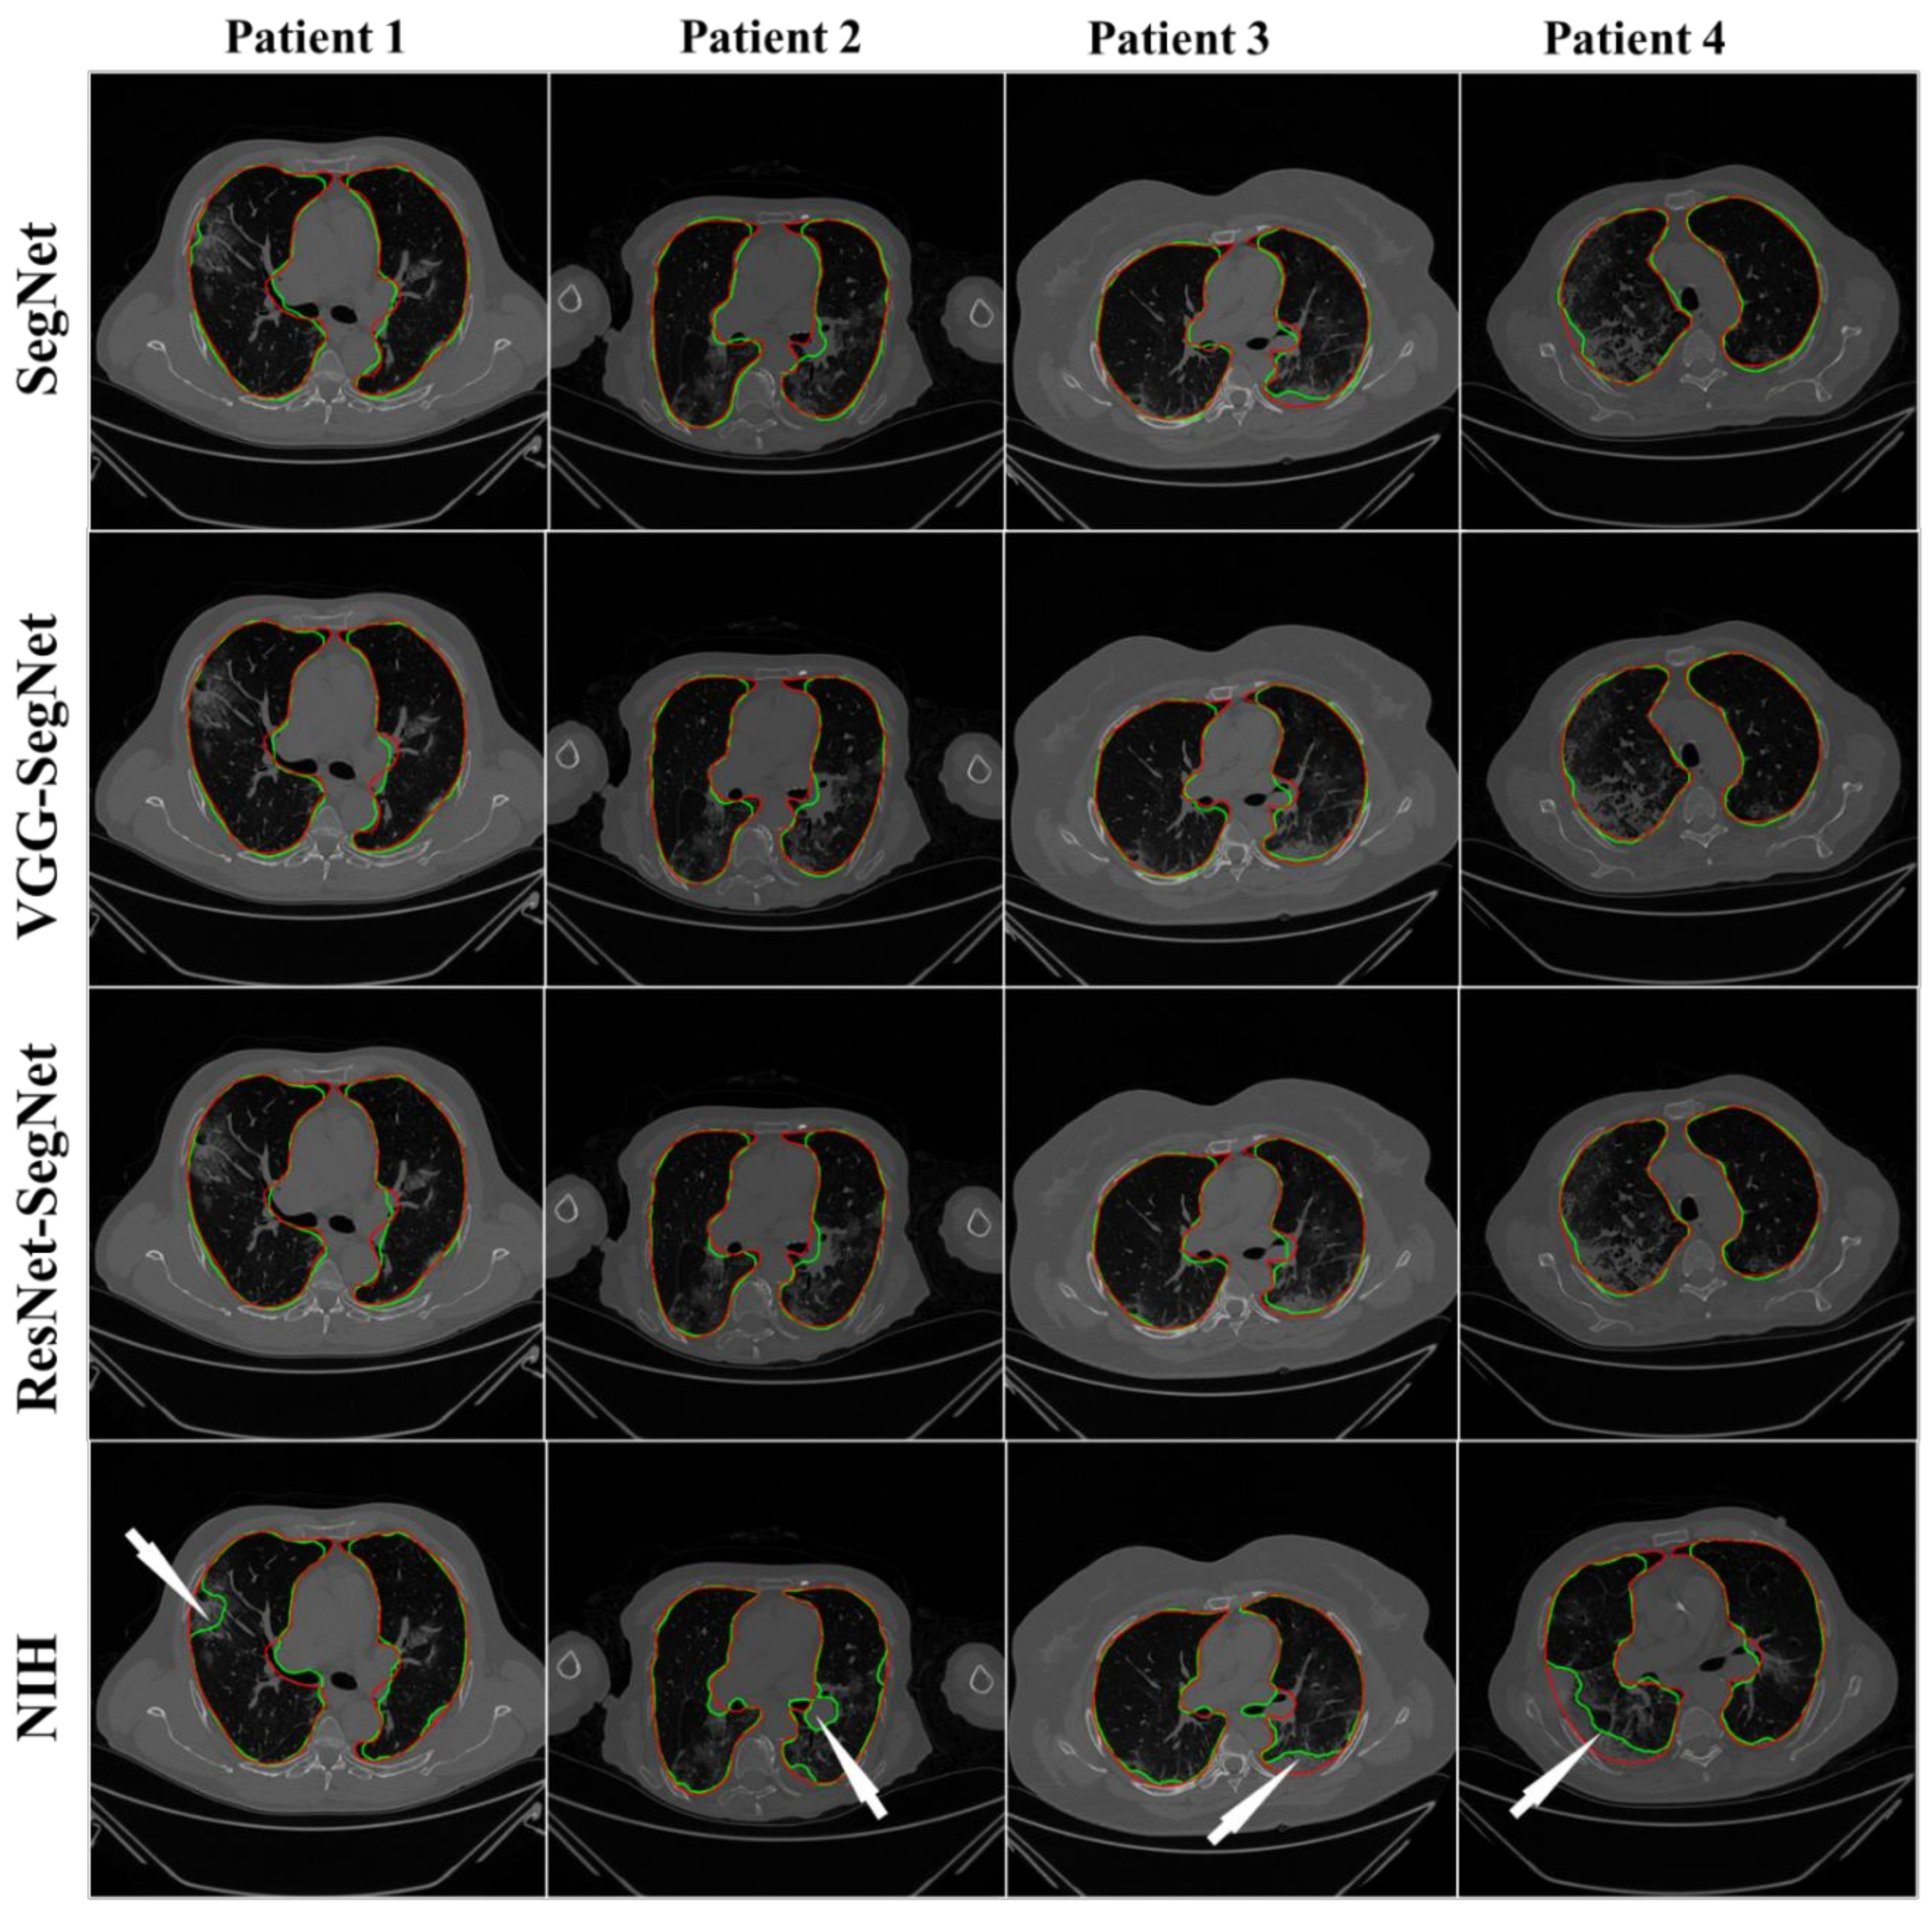

4.2.1. Visualization of Lung Boundary and Regional Lung Error